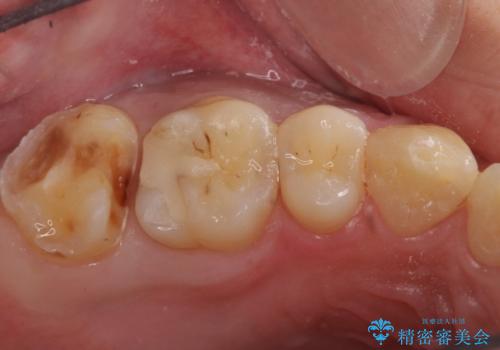

- 一番奥の銀の詰め物を白くしたいとのことで来院。

セラミックの詰め物のやりかえだと範囲が多く、割れてしまうリスクがあります。

そのため、割れるリスクが少ない詰め物ではなく、被せ物による治療(ジルコニアクラウン)を行いました。

また、隣の歯も白い樹脂の下が虫歯になっており、セラミックの詰め物(e-maxインレー)による修復をしました。